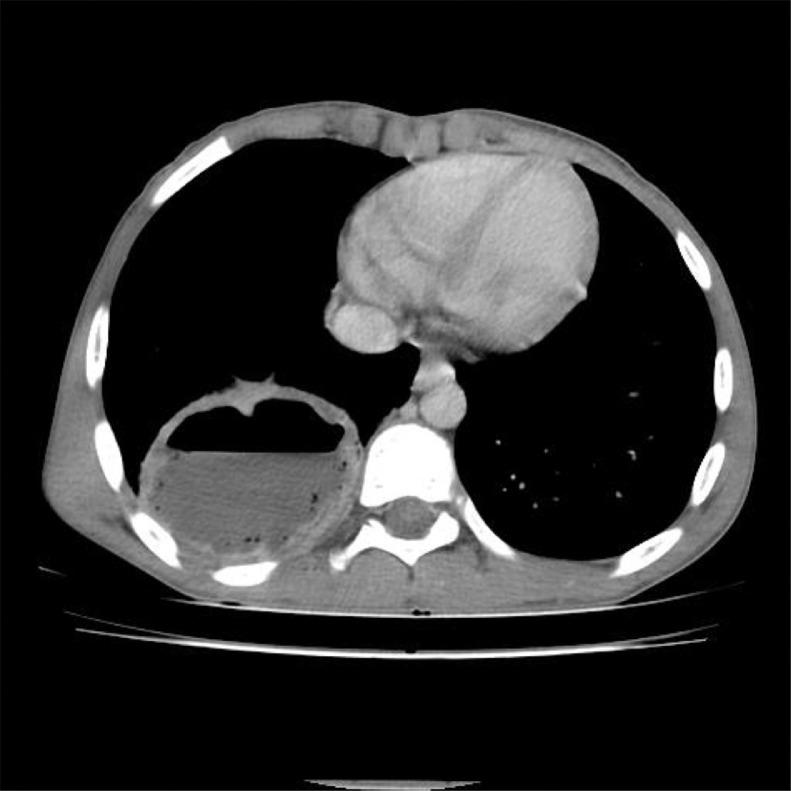

Retrocecal appendicitis usually presents with atypical signs and symptoms which may lead to delayed diagnosis, perforation and serious complications. Development of a large lung abscess secondary to perforation of retrocecal appendicitis in an adolescent patient is an extremely rare entity and to the best of our knowledge has not been described in literature. We present a 15-year-old boy with complaint of chest pain, cough, fever, vague abdominal pain and raised inflammatory markers who underwent CT examination. On CT, a collection with focal calcification was noted in the right iliac fossa that extended along the right retroperitoneum through the retrocrural space in the right lung base communicating with a cavitary pulmonary lesion with air-fluid level. A diagnosis of perforated retrocecal appendicitis with retroperitoneal and right lung abscesses was made. The patient underwent appendectomy and the entire retroperitoneal and lung abscesses were drained. A lung abscess as a complication of perforated retrocecal appendicitis should be in consideration in septic patients with thoracoabdominal infectious manifestations.